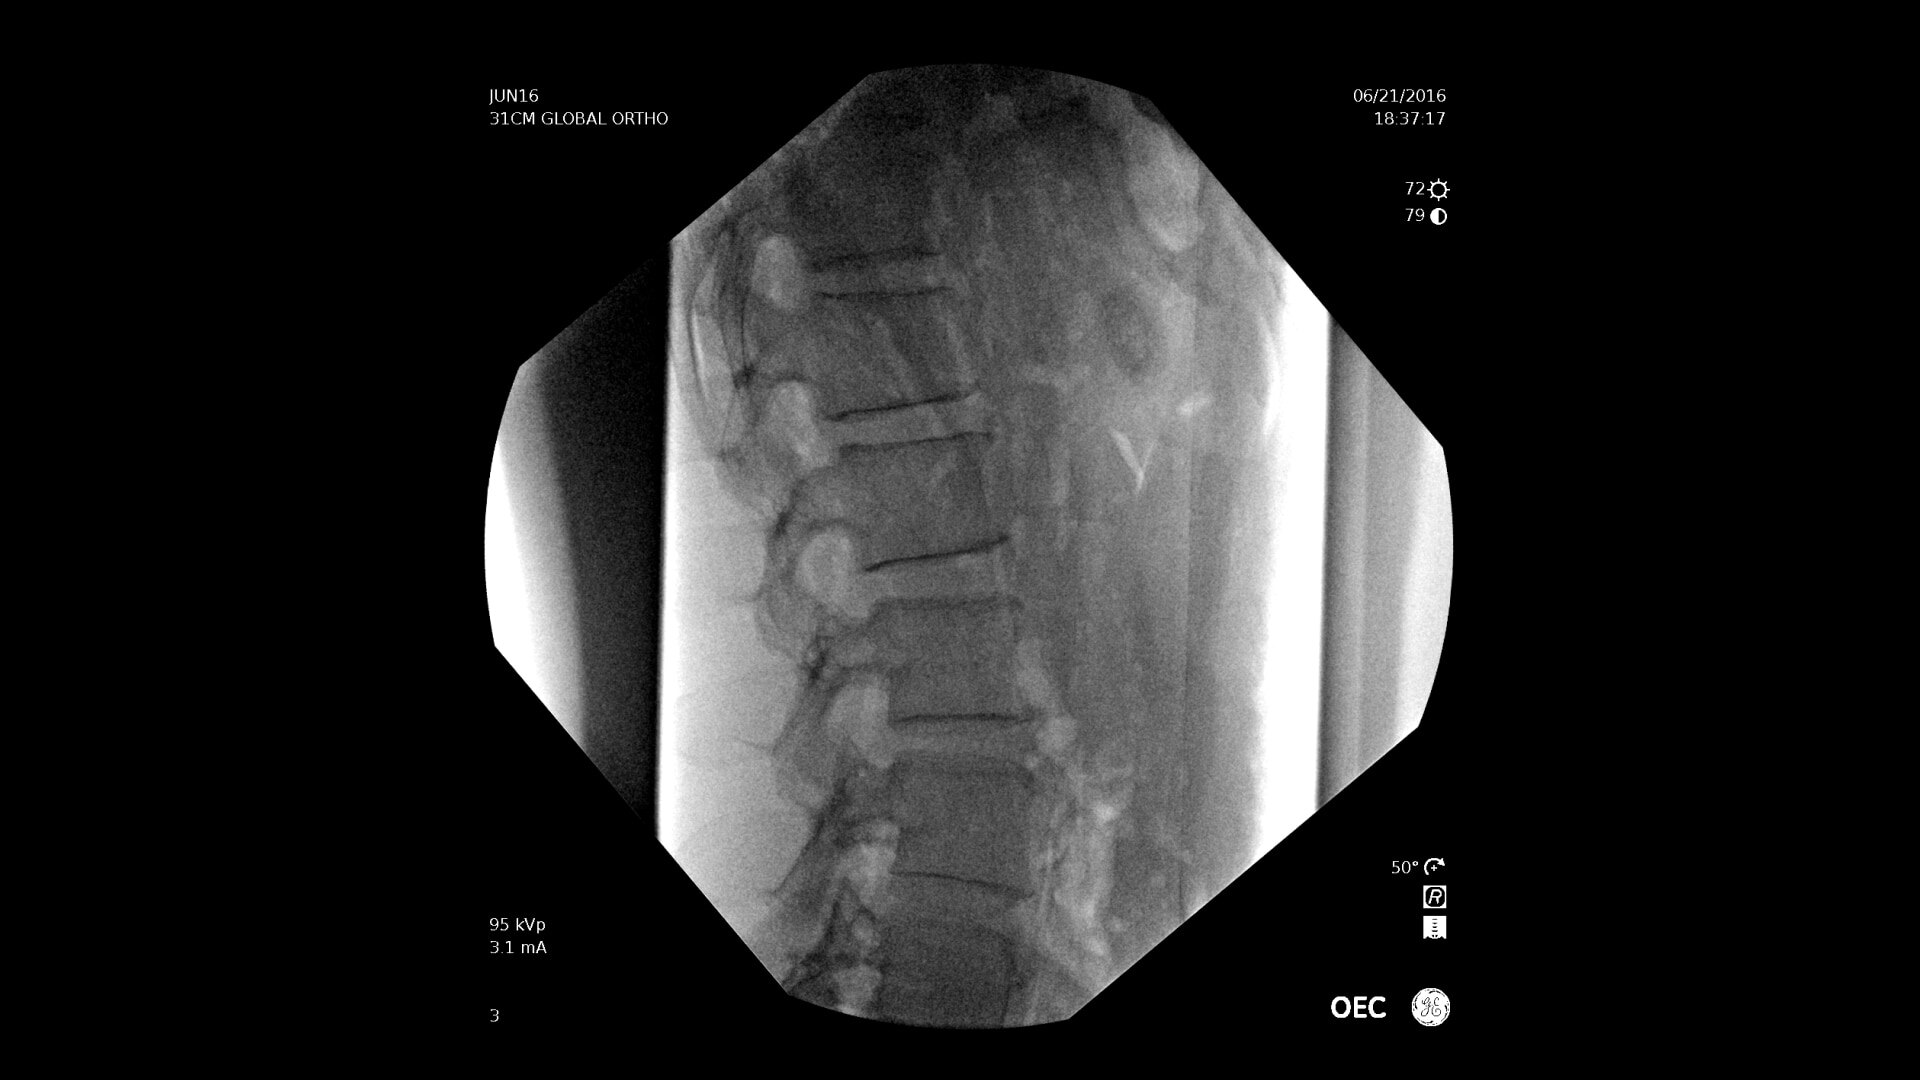

C-arms for Pain Management

Consistently experience amazing image quality, precision, and efficiency during simple to complex pain management procedures with OEC C-arms.

Achieve precision and efficiency while experiencing the image quality needed during simple to complex pain management procedures with OEC C-arms.

Pain management imaging you need

Pain Management procedures require powerful imaging systems.

OEC C-arms perform imaging in a variety of procedures such as:

• Thoracolumbar procedures